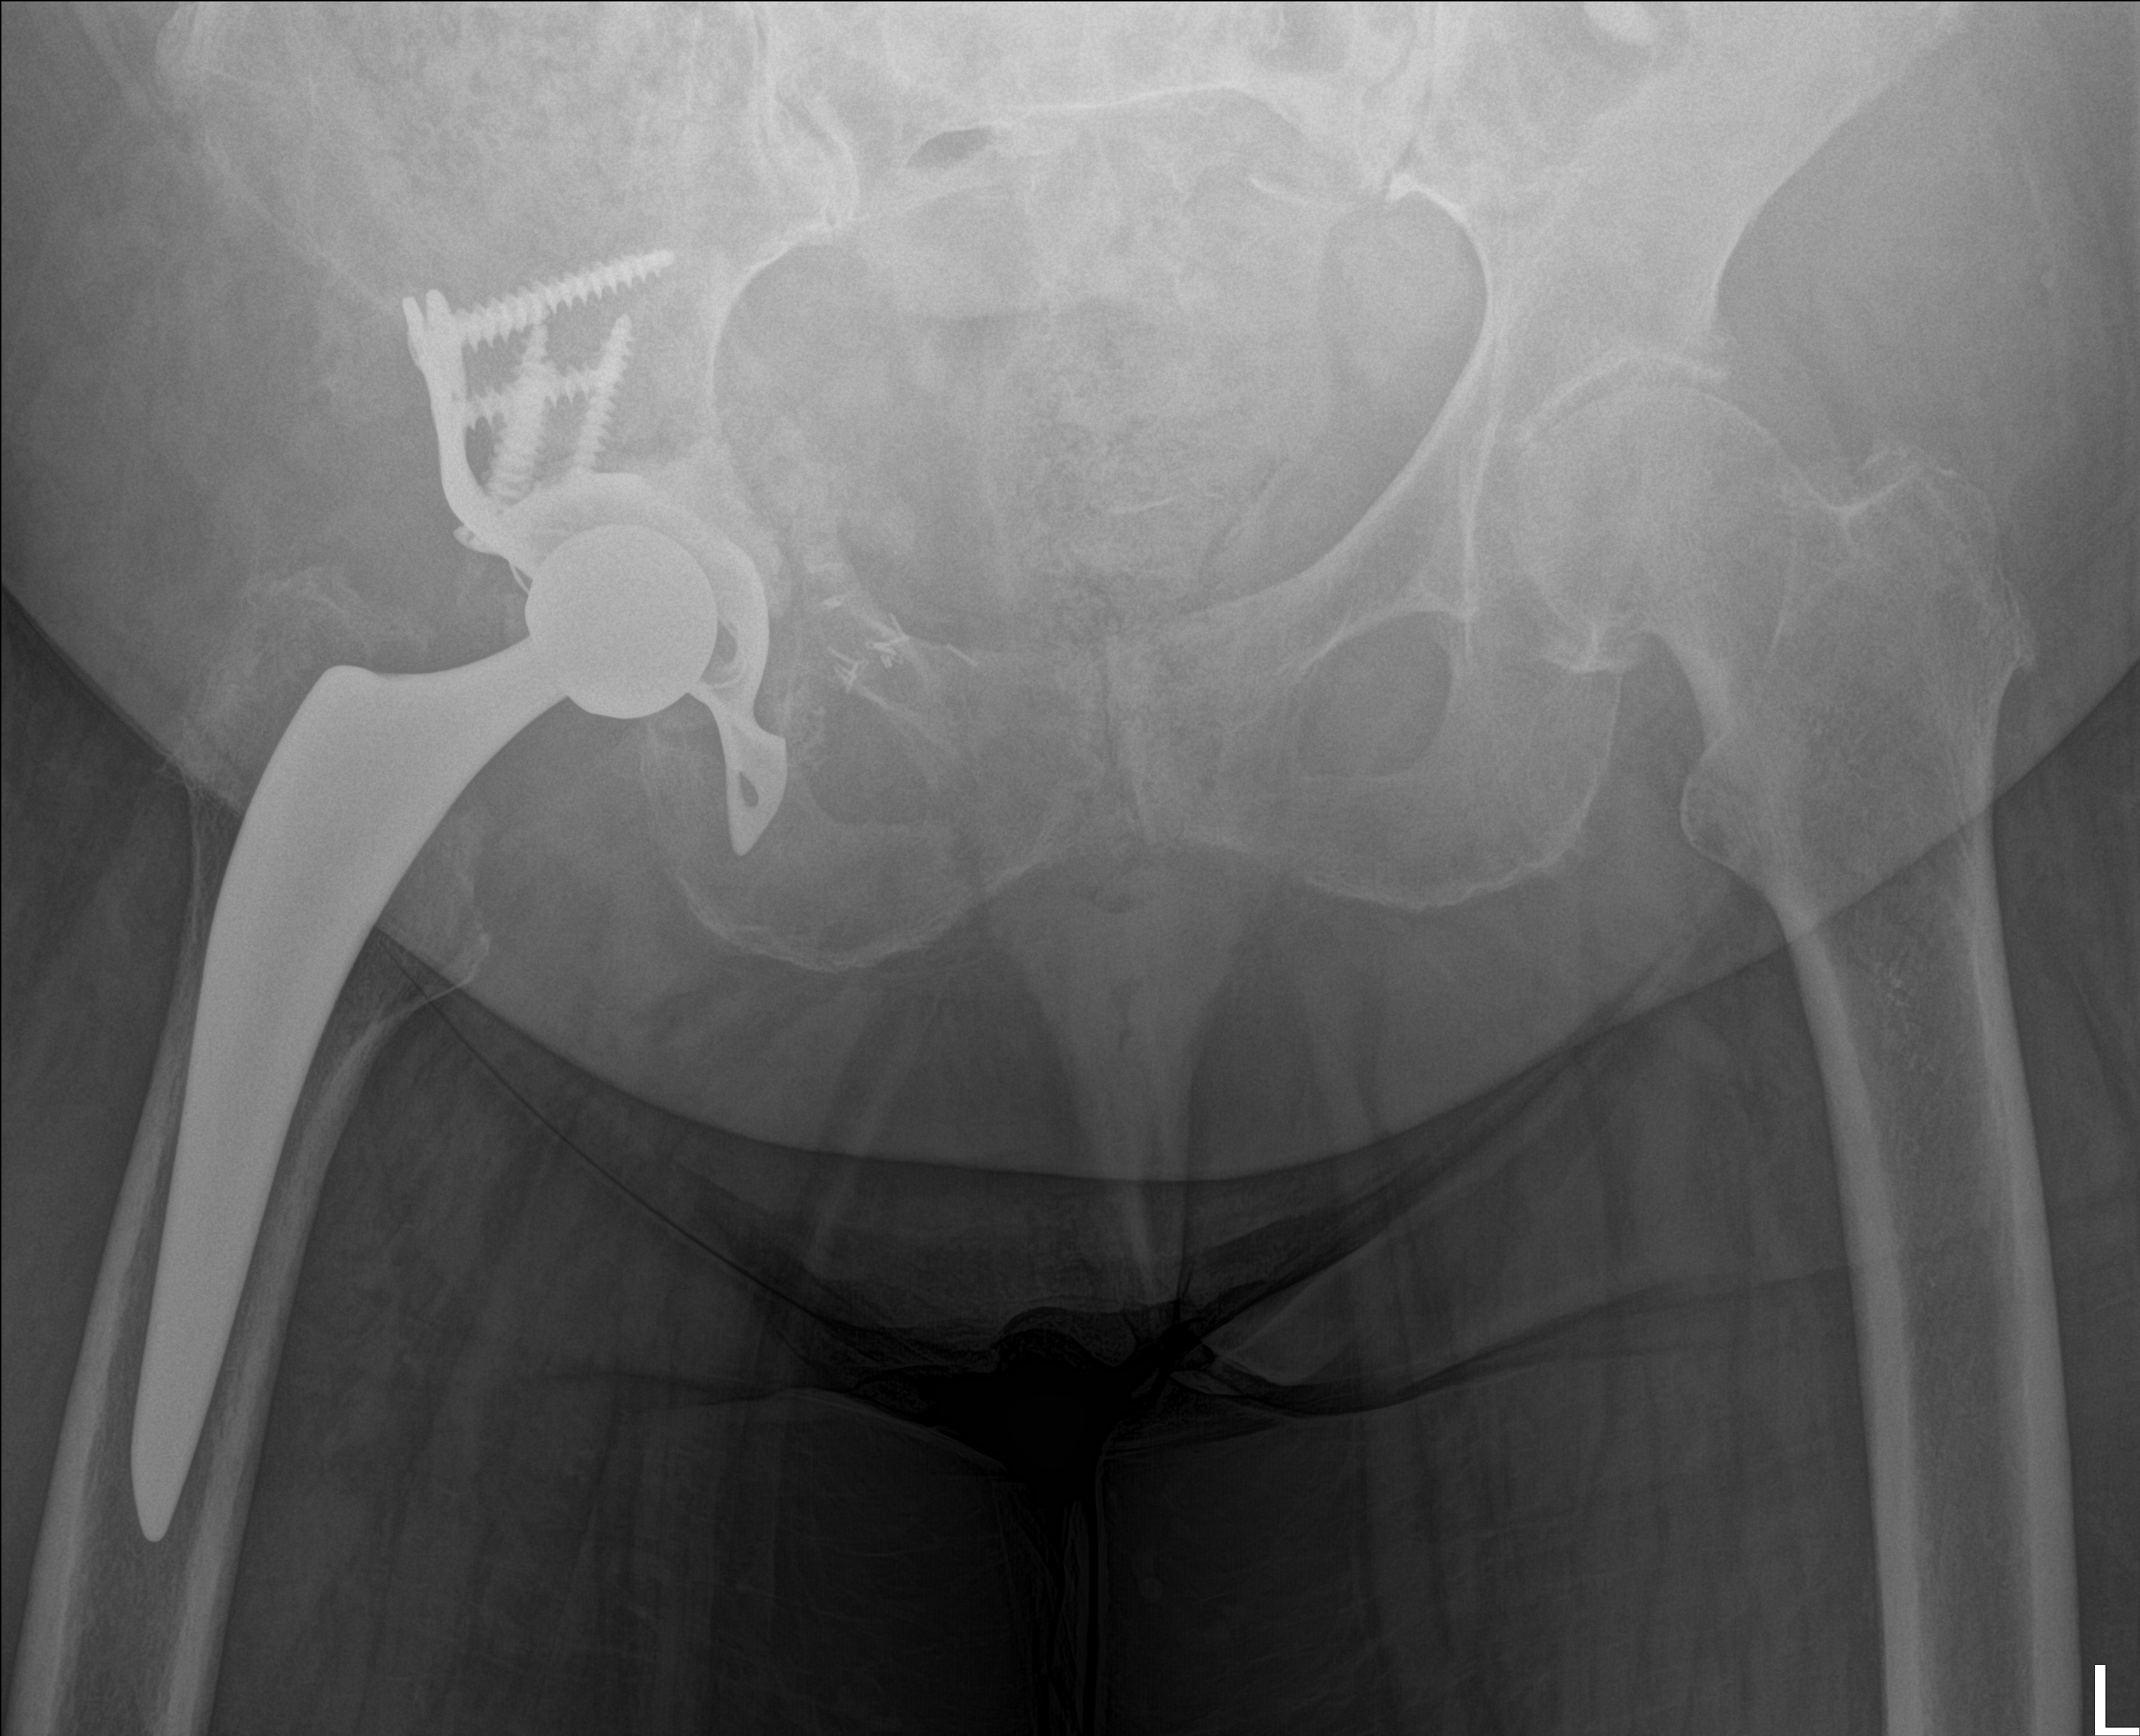

Röntgenbilder im Verlauf: korrekte Lage → Luxation → neue TEP nach Wiedereinbau

21.11.2025 - Luxiert

Röntgen November 2025

Prothesenkopf aus Pfanne luxiert

Akuter Befund: Hüftprothesen-Luxation

Vergleich der Röntgenbilder zeigt eine Luxation der Hüft-TEP rechts. Der Prothesenkopf ist aus der Pfanne ausgerenkt.

21.11.2025 - Luxation!

Becken 2025

Prothesenkopf luxiert nach medial/kaudal

Verlauf: Die Luxation/Pfannendislokation führte zur stationären Aufnahme im Universitätsklinikum Heidelberg (28.12.2025). Am 30.12.2025 wurde die TEP entfernt und ein Spacer implantiert. Infektnachweis: Enterococcus faecalis. Am 19.02.2026 wurde die neue Prothese erfolgreich eingebaut (stationär bis 05.03.2026). Komplikationsloser Verlauf, regelrechte Implantatlage im Röntgen. Entlassung mit 20kg Teillast, Amoxicillin für 6 Wochen. Wiedervorstellung am 09.04.2026.

21.11.2025

Röntgen Becken + Hüfte rechts

2 Aufnahmen | 2836x2336 px | 4.3 MB

November 2025

Aktuelle Röntgenbilder + Labor

Röntgen Becken und Hüfte rechts mit Radiologiebefunden, Laborbefund und Arztbericht

Röntgen Becken

DICOM

Luxation der Hüft-TEP

Röntgen Hüfte rechts